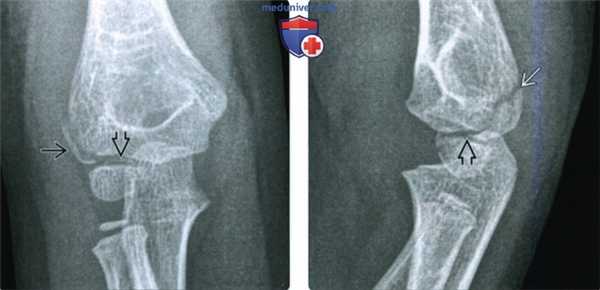

(Слева) На снимке определяется чрезмыщелковый перелом плечевой кости у женщины 63 лет после падения на выпрямленную руку. Линия перелома пересекает оба мыщелка, но не переходит на суставную поверхность. Имеется незначительное медиальное смещение дистального отломка, что является частой находкой при таких травмах.

(Справа) На фронтальной компьютерной томограмме с реформатированием без контрастирования у этой же пациентки подтверждается чрезмыщелковый ход перелома и отчетливо видно медиальное смещение дистального отломка. Кроме того, данные КТ подтверждают сохранность суставной поверхности плечевой кости.

(Слева) На передне-задней рентгенограмме перелома латерального мыщелка Милча II у взрослого пациента визуализируется линия перелома В, переходящая на локтевой сустав медиальне латерального блокового гребня. Переломы Милча II встречаются чаще, чем I тип.

(Справа) На фронтальной КТ с реформатированием у этого же пациента входная точка перелома визуализируется лучше. При локализации перелома медиальне латерального блокового гребня В он визуализируется лучше, так как повреждение Милча II типа и поэтому оно сопровождается нестабильностью локтевого сустава.